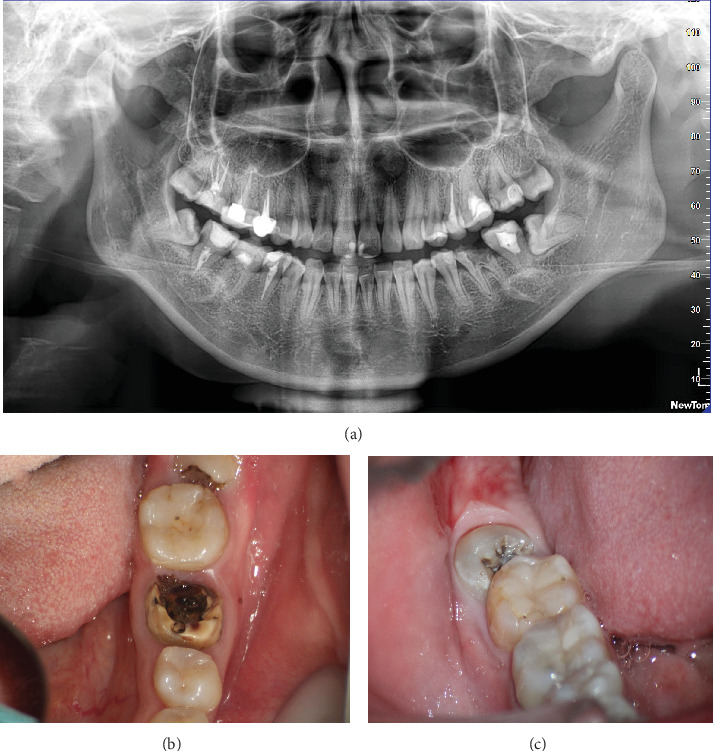

自体牙移植广泛应用于先天性缺牙或有不可逆损伤的牙的移植。本病例报告介绍了一种个性化的超声截骨术,它可以精确地准备,最大限度地减少骨创伤,增强移植牙的初始稳定性,并有助于良好的预后。手术过程如下:一名25岁的女性患者在19号牙齿上有一个瓷融合金属冠,由于严重腐烂而脱落,使牙齿无法修复。32号牙出现中等倾斜,导致31号牙腐烂。在提交治疗方案后,患者通过签署必要的文件表示知情同意,进行32号牙的自体移植以替代19号牙。第32颗牙齿被取出,并立即使用3Shape扫描仪扫描椅子。使用3D打印技术制作了一个定制的牙根形状的超声骨切开术,以匹配32号牙的形状。第19颗牙采用微创技术拔除。采用定制的3d打印超声骨切开术和计算机辅助快速成型树脂模型制备19号牙槽窝。然后将32号牙移植到牙槽内,并用8字形悬浮缝合线固定。为了防止在牙槽准备过程中因过热而损伤骨细胞和牙周组织,超声骨切开术设计了多孔水冷系统,有效地解决了这一问题。随访24个月后,移植牙符合成功标准,供体牙无病理性放光、牙根吸收或疼痛迹象。采用个性化超声截骨术制备的牙槽窝确保了与供牙的最佳贴合,保持了供牙的稳定性,并最大限度地减少了术后并发症。使用3D打印技术创建个性化的超声骨切开术代表了牙齿移植的创新进步,支持了该领域数字化和微创技术的发展。

Tooth autotransplantation is widely used to replace congenitally missing teeth or teeth with irreversible damage. This case report presents a personalized ultrasonic osteotome that enables precise preparation, minimizes bone trauma, enhances the initial stability of the transplanted tooth, and contributes to a favorable prognosis. The procedure is as follows: a 25-year-old female patient presented with a porcelain-fused-to-metal crown on Tooth #19, which had detached due to severe decay, rendering the tooth unsalvageable. Tooth #32 exhibited mesial inclination, resulting in decay of Tooth #31. After presenting treatment plan, the patient provided informed consent by signing the necessary documentation to proceed with the autotransplantation of Tooth #32 to replace Tooth #19. Tooth #32 was extracted and immediately scanned chairside using a 3Shape scanner. A custom-designed, tooth root-shaped ultrasonic osteotome was fabricated using 3D printing technology to match the shape of Tooth #32. Tooth #19 was extracted using a minimally invasive technique. The alveolar socket of Tooth #19 was prepared using the customized 3D-printed ultrasonic osteotome and a computer-aided rapid prototyping resin model. Tooth #32 was then transplanted into the socket and secured with figure-eight suspension sutures. To prevent damage to bone cells and periodontal tissues from overheating during socket preparation, the ultrasonic osteotome was designed with a porous, water-cooled system, effectively addressing this issue. After 24 months of follow-up, the transplanted tooth met success criteria, with no signs of pathological radiolucency, root resorption, or pain in the donor tooth. The alveolar socket, prepared with the personalized ultrasonic osteotome, ensured an optimal fit for the donor tooth, maintaining its stability and minimizing postoperative complications. The use of 3D printing technology to create a personalized ultrasonic osteotome represents an innovative advancement in tooth transplantation, supporting the development of digital and minimally invasive techniques in this field.